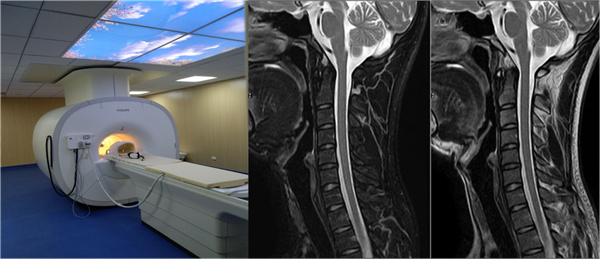

三、1.5T高场磁共振

设备型号:PHILIPS Multiva

启用时间:2017年12月

技术创新点:

1)独家mDIXON-TSE技术:单次扫描获取多种加权图像、实现完美脂肪抑制效果

2)16通道高清线圈系统:1024×1024超高分辨率成像、3MHz宽带射频技术保障信号质量

优势检查项目:

1)神经系统:DWI、MRS等高级功能成像

2)骨关节系统:软骨、韧带精细显示

3)腹部脏器:多参数定量分析

4)乳腺检查:高分辨率动态增强